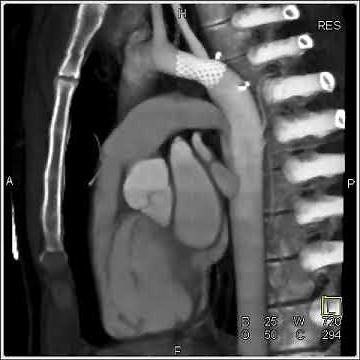

Cardiac MRI - Aorta angiogram with coarctation

已浏览 1.4万 次

2008年7月17日

YouTube

Scripps Health

CT Angiography Case06 Coarctation of Aorta

已浏览 1848 次

2018年2月16日

د. محمد عبد التواب - iShare Science